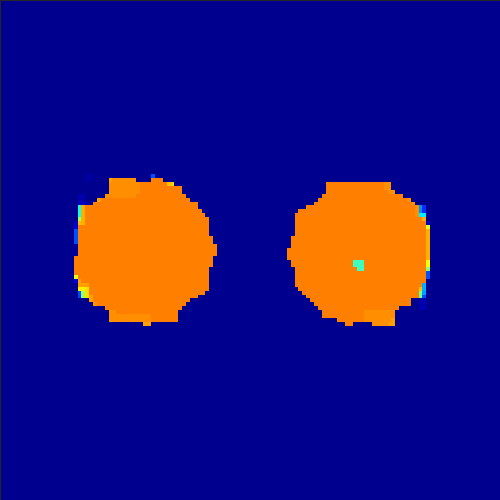

5.2 Monte Carlo Simulation

In order to test the behaviour of the proposed method in a more realistic, random-based test case, we performed a Monte Carlo simulation for dynamic SPECT imaging. First, we created a simple image phantom consisting of an outer and two inner circles which represents the structure of the region of interest (see figure 8(a)). Within those regions we assumed concentration curves over a time period of 90 time steps as displayed in figure 8(b). Based on the tracer intensity in an image frame at each time step, we created a variable number of random decay events (where the number is proportional to the average concentration in one pixel in the whole image frame per time step) with a probability proportional to the concentration in every subregion. They are detected by a virtual double head gamma camera rotating around the patient by 46 degrees per time step, which consists of 374 detector bins. Every simulated decay event is projected onto the scanner and counted by the corresponding detector bin.

In two different tests we fixed the number of events counted by the detector equal to (resp. ) times the average concentration in one pixel. The resulting sinogram images of the accumulated counts in each bin are shown in figure 9.

Based on the sinogram data we applied the proposed algorithm in order to reconstruct the original image sequence. The results for both test cases are shown in figure 10.

As one can see, the method is able to reconstruct the regions properly, even in case of a low count number. Within a number of iterations (average of 100 outer and 10000 inner iterations), the algorithm presents a reasonable reconstruction of the region of interest and the corresponding regional tracer concentration curves. Here, the parameters were not optimized as in the case of the synthesized data sets in the previous section, but kept fixed as , and . With futher optimized parameter values one could possibly provide even better results.